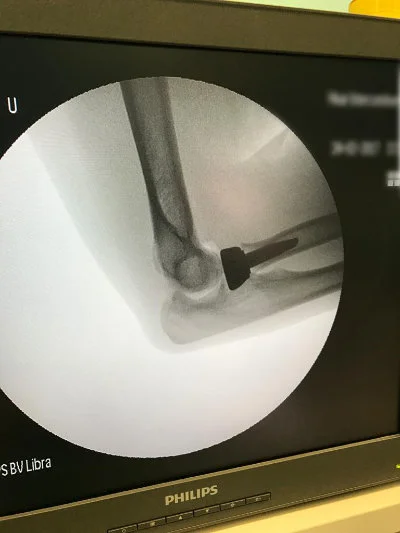

Görüntüleri büyütmek için resmin üstüne tıklayınız.